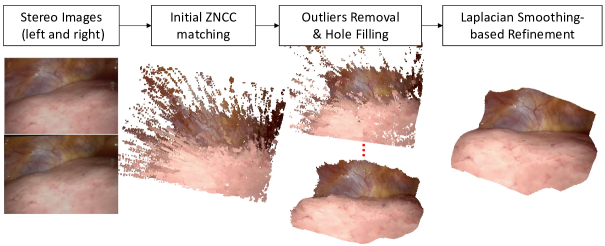

To overcome the high time complexity drawback of global stereo matching methods and difficulty to handle low texture regions of local stereo matching methods, we propose a novel stereo matching framework as shown in Fig. 1 to enlarge the radius of constraints of local stereo matching. First, we employed the zero-mean normalized cross correlation (ZNCC) metric to evaluate similarities between local image patches to estimate disparities of pixels. Then, we developed a robust outliers removal and hole filling method to refine the ZNCC matching results. The first two steps provide discrete initial disparity values that are from the candidate disparities pool for the final refinement step, where we integrate the ZNCC metrics and the smoothing cost into a modified Laplacian smoothing framework. This method is able to build large connections among pixels when minimizing the cost function, and is easier to compute than conventional Gauss-Newton (GN) or Levenberg-Marquardt (LM) algorithms. It is worth clarifying that we are not implying that ZNCC is the best metrics, however since our stere matching methods are mostly post-processing steps, it is easy to replace ZNCC with other local matching metrics. The algorithms in our stereo matching method work in parallel with respect to each pixel, and are highly appropriate for GPU parallel computing.

II-B Outliers Removal and Hole Filling

The initial ZNCC matching may result in a large amount of outliers. Our outliers removal and hole filling method is under a reasonable assumption that the tissue surface is relatively smooth. Hence, an inlier should have sufficient number of neighboring points that has smooth change of disparities. Denoting as the detection radius, we detect along each 8-radial directions within radius and check if the disparity of two neighboring points is smaller than a pre-defined threshold ( in our experiments). If none of the 8-radial directions satisfies this smooth disparity assumption, the point will be recognized as an outlier and removed.

We developed two hole filling methods. For a left-image pixel that cannot find its corresponding right-image pixel, the first method searches along the pixel’s 8-radial directions and the second method searches within a radius of the pixel. In our experiment the two radii for the hole filling methods are fixed, which are 50 and 20 pixels respectively. If sufficient number of neighboring points have a valid disparity value, then disparity of this pixel is filled according to interpolation. In the hole-filling step the iterations are performed within a radius, which avoids interpolation at distant areas.

However, when removing outliers, it is difficult to pre-define a radius for all cases. A small may keep too many outliers and a large may remove inliers. To removal outliers and preserve as many inliers as possible, we propose to use an iterative process that alternately performs outlier removal and hole filling, as shown in Fig. 1(a). In this process we gradually enlarge with a step when detecting outliers. Hence, disparities that are removed may then be filled, and neighboring inliers will not be removed with larger . In our experiments, the number of outliers removal and hole filling iterations is 3; the radius is 10 pixels initially and increases at a step of pixels.

II-C Improved Laplacian Smoothing-based Refinement

Further step to refine the estimated disparities is necessary because (1) the initial disparities after the first two steps are discrete values that are directly selected or interpolated from the candidate disparities and (2) relationships among pixels are not fully considered. Our refinement method is based on Vollmer’s improved Laplacian smoothing method [36], which is able to avoid model shrinking compared with standard Laplacian smoothing. We integrate a cost function that consists of the ZNCC metrics and the smoothing cost into this improved Laplacian framework to allow for dynamically updating the disparities. The details of our refinement step are as follows: